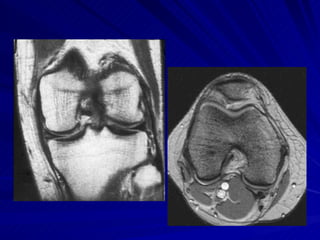

Osteocondrite dissecante